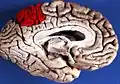

Precuneus of left cerebral hemisphere (shown in red).

Medial surface of left cerebral hemisphere. (Precuneus visible at top left.)- Medial surface of left cerebral hemisphere. (Precuneus colored in red.)